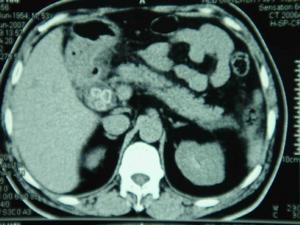

腦豬囊尾蚴病影像寄生於腦室系統的囊蟲大小不一,在第四腦室最多見,病灶可單發或多發,可游離於腦室亦可黏附於腦室壁上。此類囊蟲易形成活瓣或引起腦膜粘連增厚而阻塞腦室孔,產生梗阻性腦積水,腦室擴大,晚期可導致腦萎縮、顱內高壓、腦疝等嚴重後果。

其他輔助檢查:頭顱平片可發現已鈣化的囊蟲結節,陽性率為10%左右。CT的陽性率則可高達90%以上。不同病期的腦囊蟲在CT上的表現差異很大,當囊蟲寄生於腦實質時,典型的有以下4種表現:①小的鈣化灶或肉芽腫,反映了死亡的囊蟲;②圓形的低密度灶,造影后不被增強,反映了活的蟲體;③低密度或等密度的病灶,造影后有環狀強化,反映了囊蟲導致的腦部炎症;④大腦瀰漫性水腫,伴有腦室縮小及多發的造影后可增強的小結節(造影前不能發現)。當蟲體寄生於蛛網膜下腔時,CT上主要表現為腦脊液通路受阻引起的腦水腫,蛛網膜炎引起的大腦幕和腦底池異常增強以及多發性的腦梗死和腦橋池、交叉池、大腦側裂等處的低密度灶。